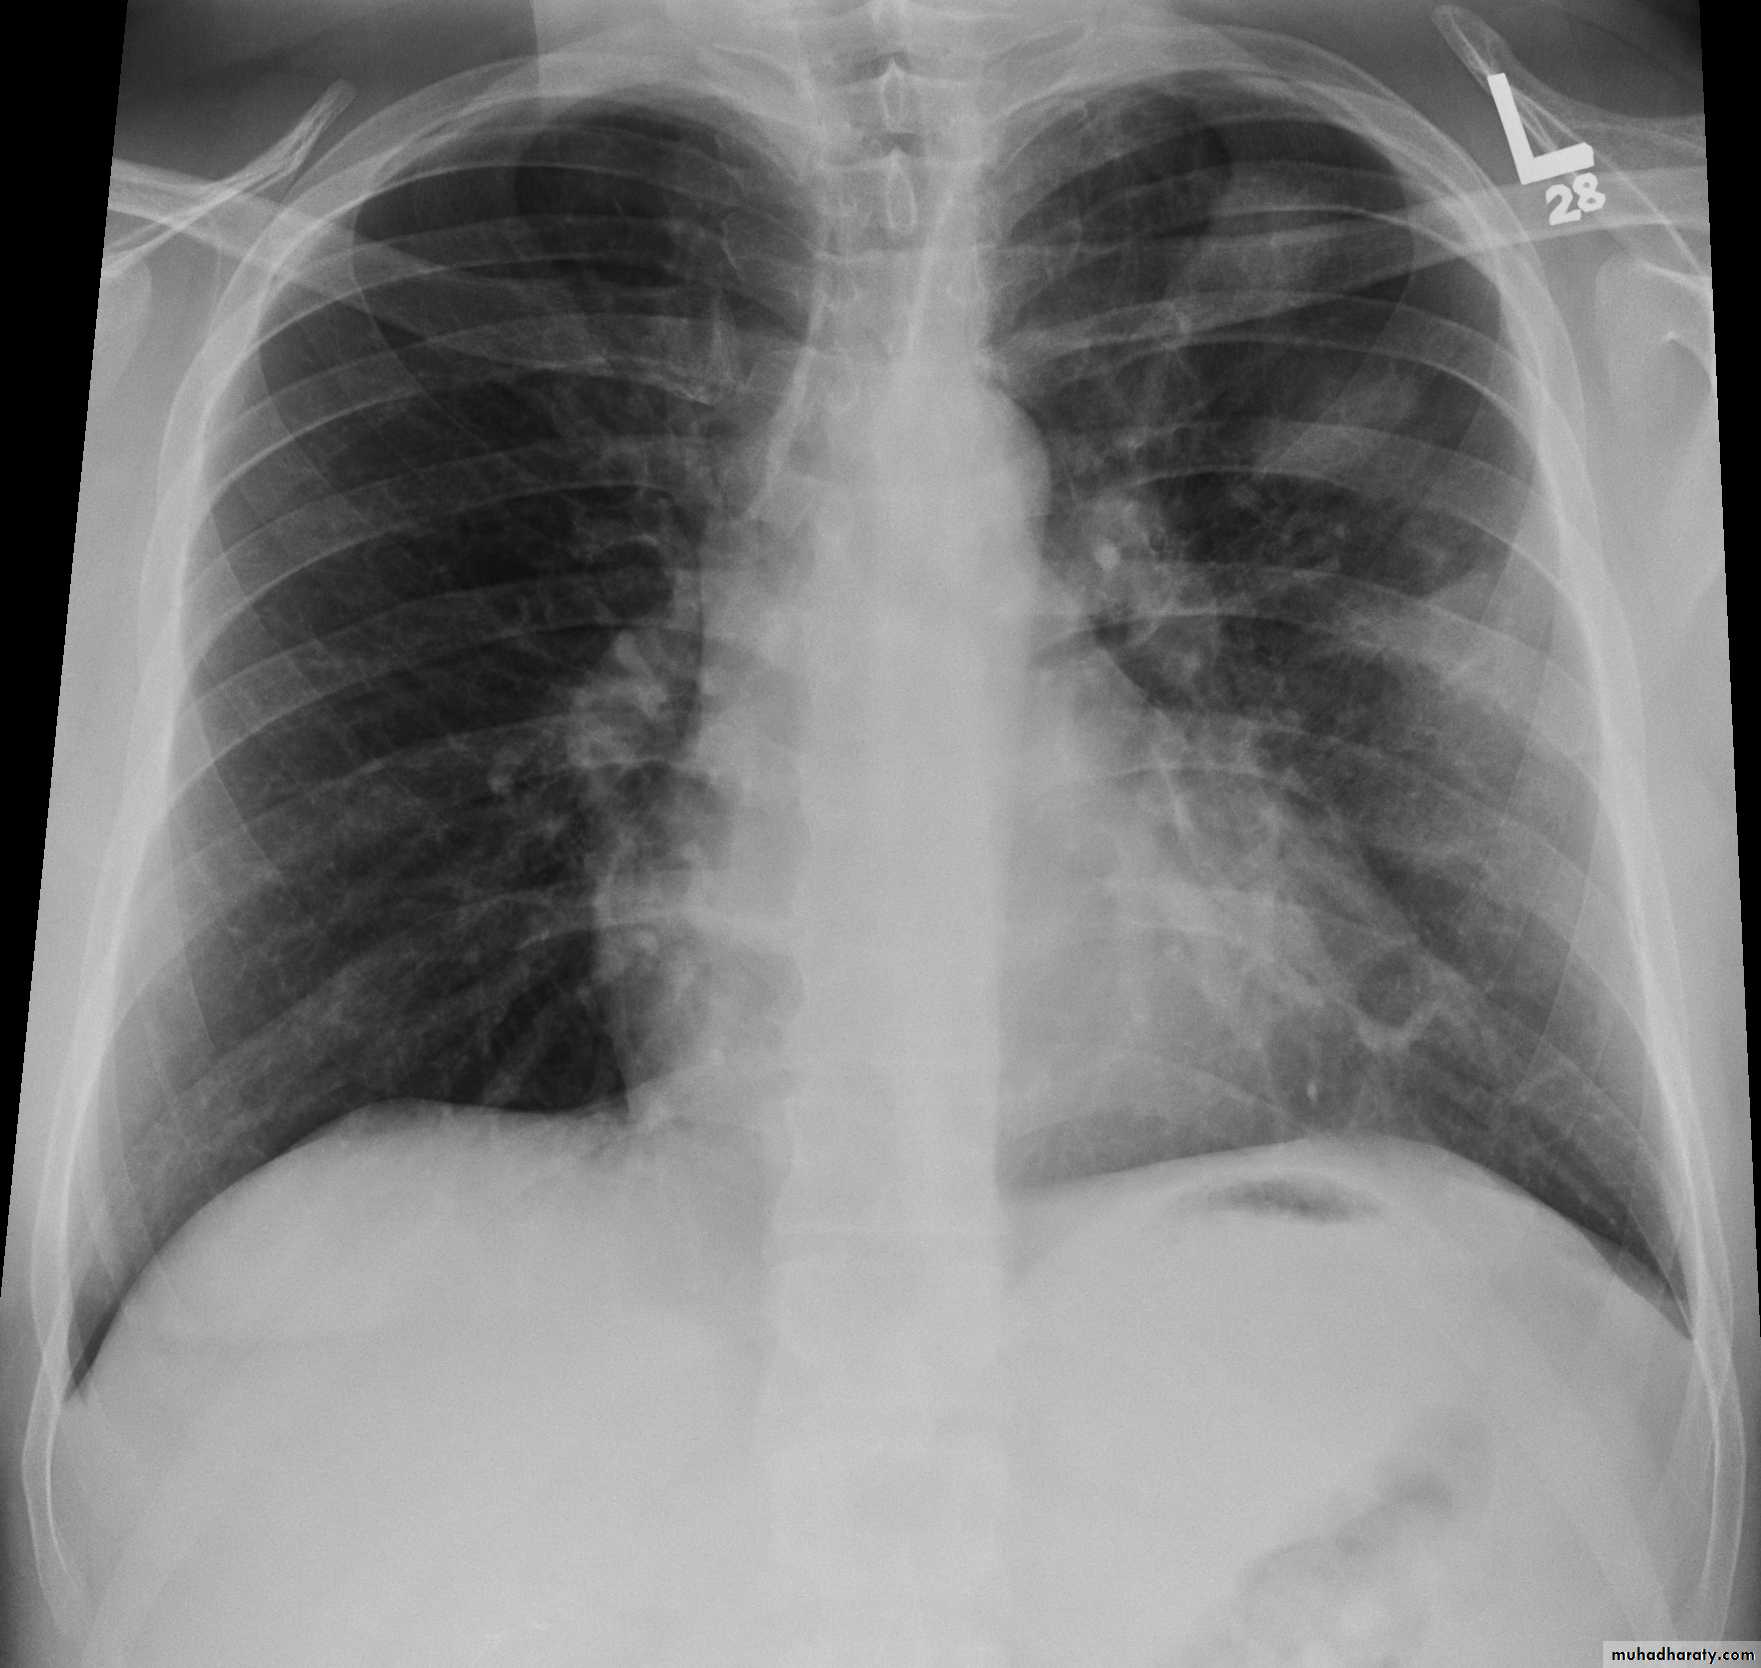

• CXR oligemia or linear or triangular consolidation,